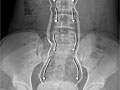

- Una tomografía computarizada (CT, por sus siglas en inglés) espiral sin contraste es un tipo especial de tomografía computarizada que se mueve en círculos.

- Una ecografía usa ondas de sonido reflejadas para producir una imagen de las vías urinarias.

- Una pielografía intravenosa (IVP, por sus siglas en inglés) es una radiografía que muestra imágenes de las vías urinarias, incluyendo los cálculos renales.

- Una pielografía retrógrada usa un tinte para averiguar si un cálculo renal o alguna otra cosa está obstruyendo las vías urinarias.

- Una radiografía abdominal (de los riñones, de los uréteres y de la vejiga [KUB, por sus siglas en inglés]) proporciona una imagen de los riñones, de la vejiga y de los conductos que conectan los riñones con la vejiga (uréteres).